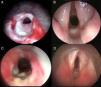

La estenosis subglótica es una de las causas más frecuentes de obstrucción laríngea. El 90% resultan de la intubación endotraqueal. La conducta terapéutica dependerá entre otros factores del grado de estenosis que se presente. Variará desde la conducta expectante en los grados leves hasta la cirugía compleja en los graves. Presentamos nuestra experiencia en el manejo quirúrgico de la estenosis subglótica postintubación en niños, y enfatizamos la necesidad de reconocimiento y prevención de los factores predisponentes de la estenosis por intubación.

MétodoSe evaluaron en forma retrospectiva 71 pacientes con estenosis subglótica moderada a severa postintubación, operados en el Servicio de Endoscopia Respiratoria durante un periodo de 8 años. Las variables analizadas fueron la edad al momento quirúrgico, el grado de la estenosis, la técnica quirúrgica utilizada, las complicaciones y los resultados.

ResultadosEl 84,5% de los pacientes requirió un solo tratamiento quirúrgico para lograr la decanulación. Se implementaron 3 técnicas quirúrgicas: reconstrucción laringotraqueal, resección cricotraqueal parcial y división anterior del cricoides. Se logró la decanulación en 70 casos, presentando buena ventilación, deglución y voz el 71,8%, disfonía el 23,9% y dificultad respiratoria leve el 2,8%. Un paciente falleció.